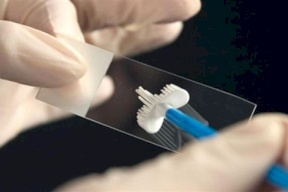

اكتشاف طريقة جديدة للتأقلم مع السكري

صدى نيوز - اكتشف علماء جامعة كونيتيكت الأمريكية، أن إزالة الخلايا القديمة في الأنسجة الدهنية للإنسان، يخفض من علامات النوع الثاني من مرض السكري.

وتشير مجلة Cell Metabolism، إلى أن الطريقة الجديدة ستساعد على علاج مختلف أمراض التمثيل الغذائي.

وكما هو معروف خلايا الجسم في تجدد مستمر. ولكن هذ...